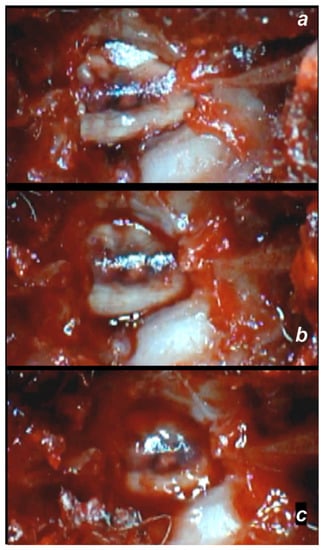

Early Post-Injury Course, Immediate Effect

Delayed Post-Injury Course, Immediate Effect